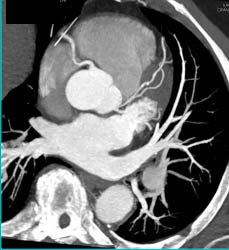

Minimal Plaque in LAD